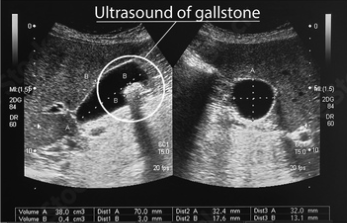

Ecografía abdominal: Es la técnica de imagen más utilizada y efectiva para detectar cálculos biliares y observar la inflamación en la vesícula.

Ecografía Abdominal para detectar cálculos biliares y evaluar la inflamación.